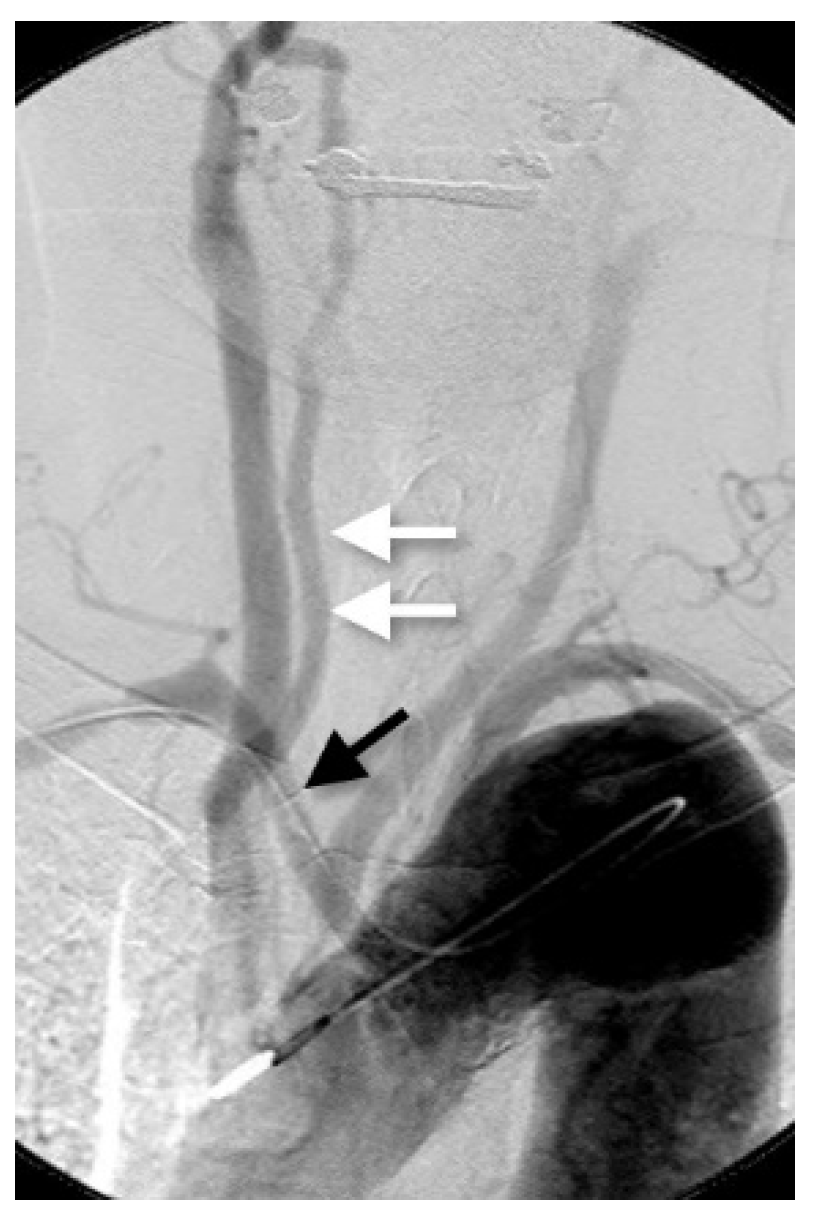

3.2. Right VA Originating from the Common Carotid Artery or the Brachiocephalic Artery